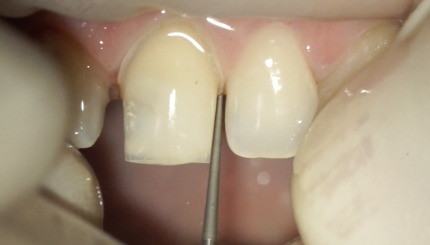

Оттиск под вр. коронки +фиксация

10 августа 2021